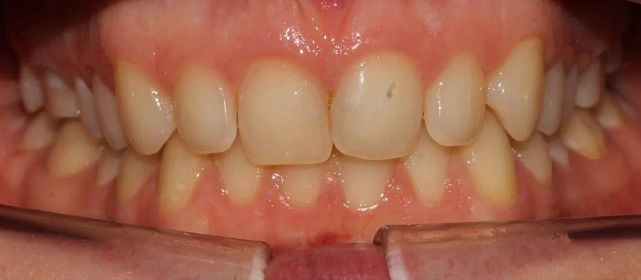

Результат

полное выравнивание зубных рядов без удаления зубов. Рецессия десны не прогрессировала (контроль по КТ через 12 месяцев). Пациентка носит несъёмные ретейнеры

и ночные капы.

Ход лечения

общий срок — 18 месяцев, 11 визитов для замены дуг и контроля. На 4-м месяце — видимое улучшение выравнивания. На 12-м — начат этап коррекции прикуса

с межчелюстными эластиками. На 18-м — снятие, установка ретейнеров.